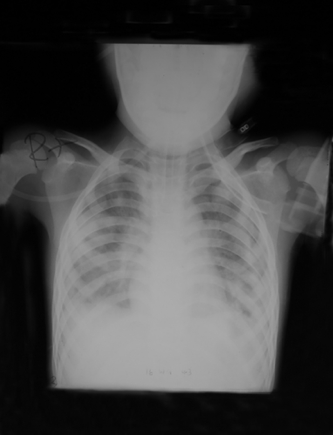

Lung of a child in respiratory failure and needs respirator for assist ventilation |